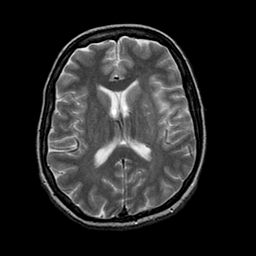

Tour 1: Next/Previous/Start: This is a tour of brain images from a 45 year-old woman who noticed the sudden onset of right body weakness and trouble speaking at about 400 PM. At the hospital, Roentgen-ray CT was normal, and the conventional T2-weighted MR image acquired 8 hours after onset of symptoms showed only subtle changes, appreciated only in retrospect. (Click the buttons at left to check adjacent slices.) Diffusion-weighted MR (below) showed a large area of abnormal signal in the region clinically suspected: the portion of left hemisphere supplied by the middle cerebral artery. It is important to note that the method of diffuson imaging shown here does not require specialized hardware. For details of the method, see published abstract describing the line scan diffusion method.